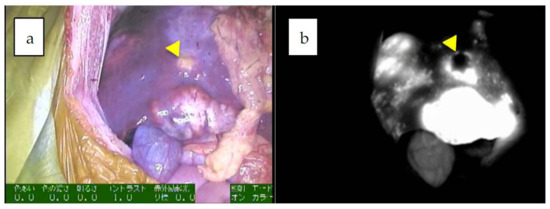

- Souzaki, R.; Kawakubo, N.; Matsuura, T.; Yoshimaru, K.; Koga, Y.; Takemoto, J.; Shibui, Y.; Kohashi, K.; Hayashida, M.; Oda, Y.; et al. Navigation surgery using indocyanine green fluorescent imaging for hepatoblastoma patients. Pediatr. Surg. Int. 2019, 35, 551–557. [Google Scholar] [CrossRef] [PubMed]

| 5 | 5 | 4y/M | PDE neo system | LDLT 2 | combined fetal and embryonal subtype, post-chemotherapy | uneven | 90 mm | 42591 | identification, surgical margin, newly detected tumors, 19 m |

| 8 | 8 | 14y/M | PDE neo system | partial resection (recurrences in the transplanted liver) | wholly epithelial type and fetal subtype | diffuse | 8 mm | 69 | identification, surgical margin, newly detected tumors |

| 9 | 8 | 14y/M | PDE neo system | LDLT 2 | wholly epithelial type and fetal subtype | diffuse | 8 mm | 394 | identification, surgical margin, 34 m |